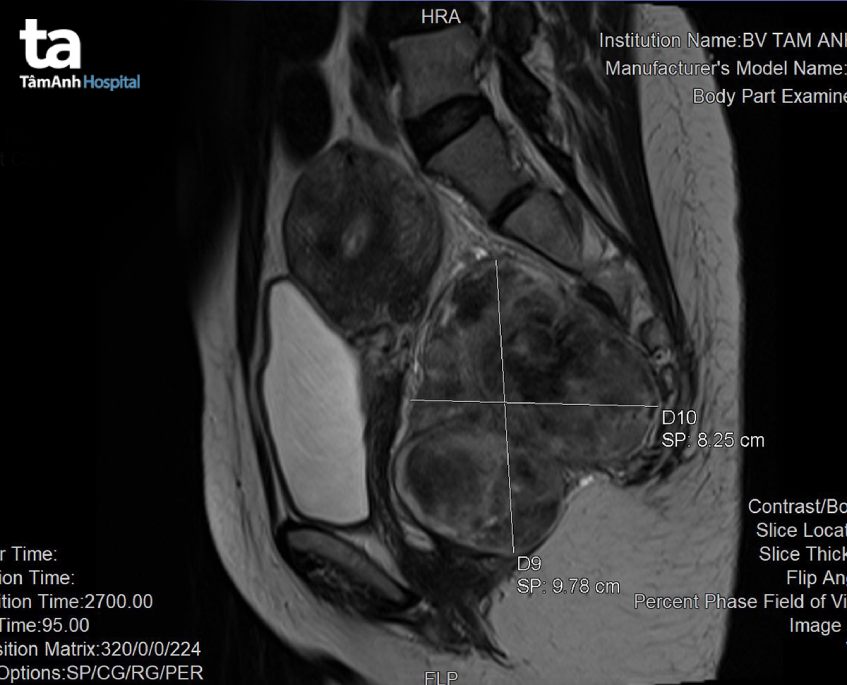

TS.BS Đỗ Minh Hùng – Giám đốc Trung tâm Nội soi và Phẫu thuật nội soi tiêu hóa cho biết, khi kiểm tra hậu môn – trực tràng đã phát hiện một khối u rất to và cứng. Người bệnh được cho thực hiện nội soi đại tràng gây mê, xác định khối u không nằm bên trong đại tràng. Kết quả chụp MRI vùng chậu tại Trung tâm Chẩn đoán hình ảnh đã cho thấy khối u có kích thước khoảng 8 – 10cm nằm ở vị trí khó phẫu thuật, sau trực tràng và trước xương cùng cụt, một phần khối u được nhận định có vẻ đã xâm lấn vào mạch máu trước xương cùng cụt.

Dựa vào phim chụp MRI và kinh nghiệm nhiều năm điều trị các bệnh u đường tiêu hóa từ đơn giản đến phức tạp, bác sĩ Minh Hùng nói thêm, chúng tôi nghi ngờ đây là một dạng u mô đệm đường tiêu hóa (GIST). Tất nhiên, để có kết luận chính xác thì cần phải thực hiện sinh thiết tế bào. Ở trường hợp bệnh nhân Mai, chúng tôi không tiến hành chọc sinh thiết để tránh gây ra tình trạng phát tán tế bào, mà chờ sinh thiết sau khi mổ.